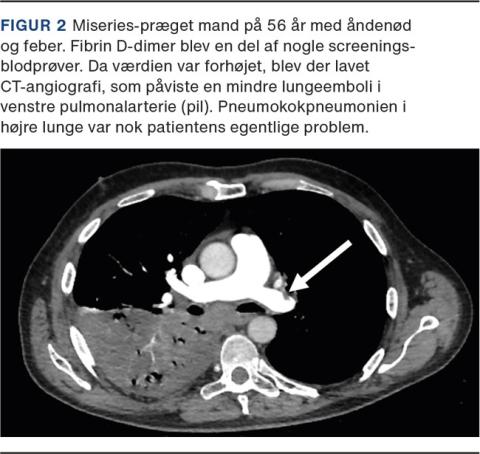

D-dimer er en akut fasereaktant og er forhøjet ved inflammationstilstande og infektioner [20]. En forhøjet D-dimer hos en inficeret, men ellers upåvirket patient kan derfor foranledige unødvendig udredning for lungeemboli. Man bør også huske, at forekomsten af incidentelle lungeembolier, som findes ved CT’er lavet på anden baggrund, er betydelig [21]. Da infektionssygdomme i sig selv disponerer til venøs trombose, skal man derfor have proportionerne i orden (Figur 2). Fund af lungeemboli uden klinisk betydning kan resultere i blodfortyndende behandling, uden det har påviselig effekt. Man kan sågar ende med anbefaling om livslang direkte oral antikoagulant i reduceret dosis, når der nu ikke var en oplagt årsag til lungeembolien [22]. Dette kan betyde, at patienten får øget blødningsrisiko på lang sigt grundet et tilfældigt fund [22].

Billede